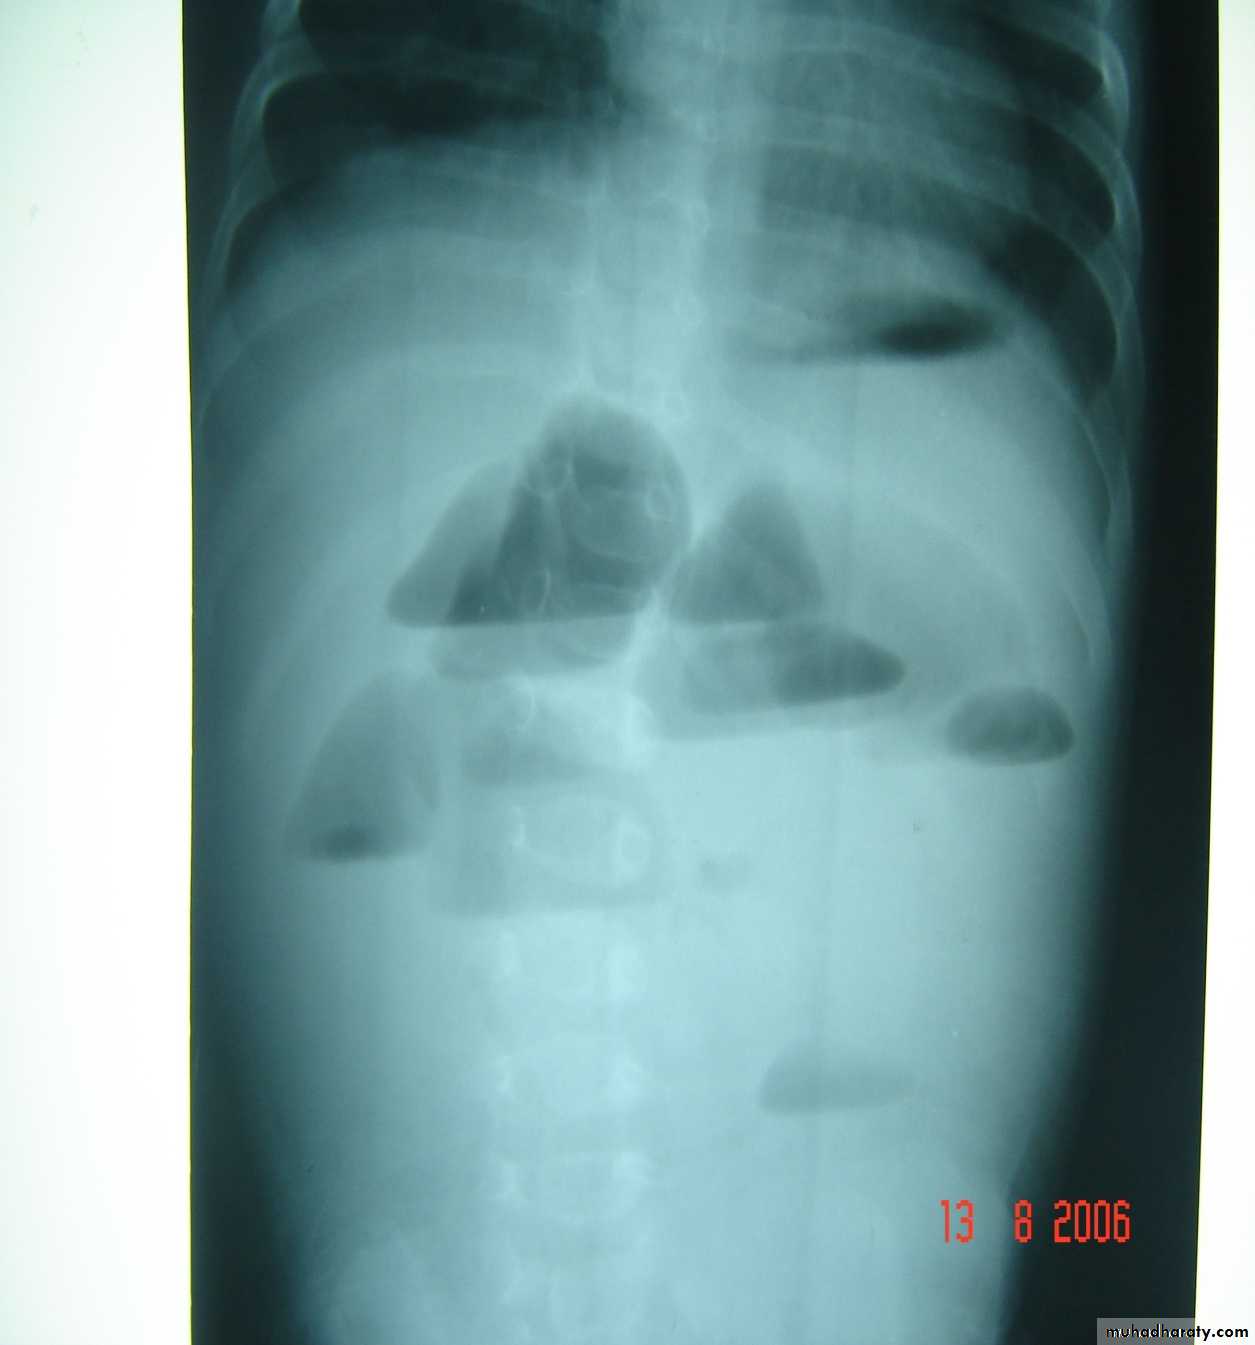

Bowel Obstruction

web